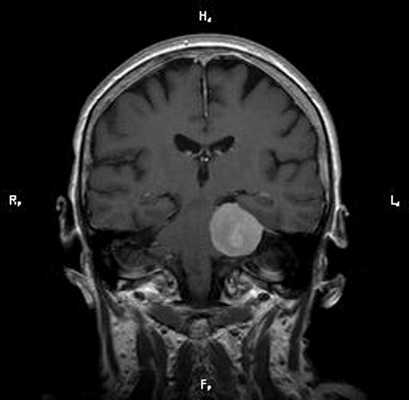

Пациент Р. 62 лет

Проблема: жалобы на частые головные боли, снижение слуха (левое ухо), а также шум в ушах (больше слева). Пациент был направлен на МРТ головного мозга в ЦМРТ с целью уточнения диагноза.

Диагноз: Онкология. Менингиома мосто-мозжечкового угла

Врач ЦМРТ

При МРТ головного мозга в левом мосто-мозжечковом углу определялось больших размеров округлой формы внемозговое патологическое образование, с четкими ровными контурами, широким основанием, прилежащее к твердой мозговой оболочке. После внутривенного контрастирования отмечалось равномерное, выраженное усиление интенсивности МР-сигнала от вышеописанного образования, а также твердой мозговой оболочки. Пациенту был поставлен диагноз (менингиома левого мосто-мозжечкового угла).